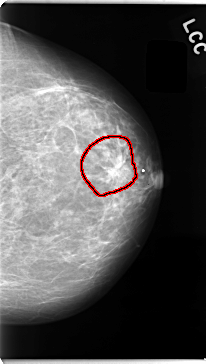

C_0059_1.LEFT_CC

LEFT_CC LINES 4720 PIXELS_PER_LINE 2672 BITS_PER_PIXEL 12 RESOLUTION 50 OVERLAY

FILE: C_0059_1.LEFT_CC.OVERLAY

TOTAL_ABNORMALITIES 1

ABNORMALITY 1

LESION_TYPE MASS SHAPE IRREGULAR MARGINS SPICULATED

ASSESSMENT 5

SUBTLETY 5

PATHOLOGY MALIGNANT

TOTAL_OUTLINES 1

BOUNDARY